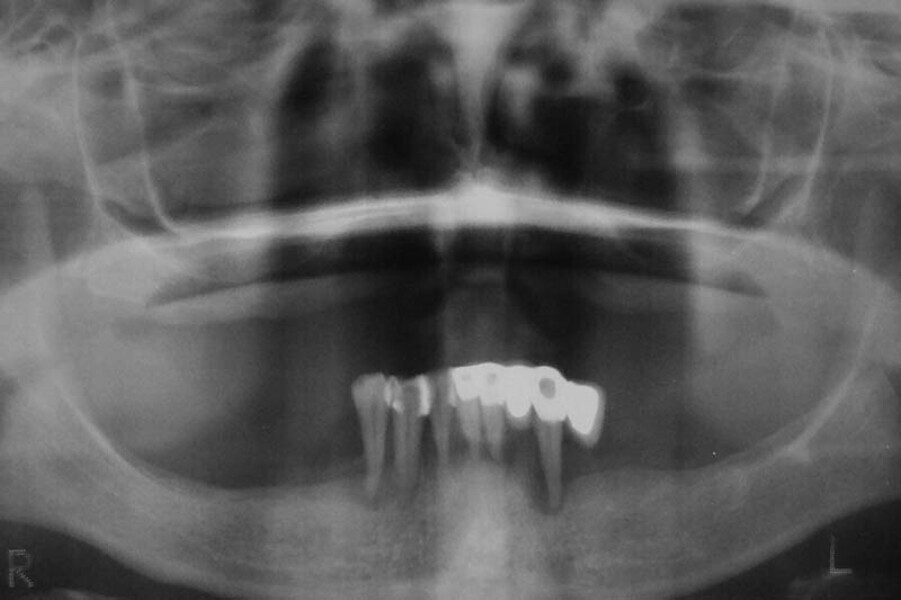

Fig. 16. Rx Pre-operatoria, Prótesis híbrida inmediata con 6 años de evolución y Rx Control a los 6 años.

Fig. 17. Rx Pre-operatoria, Prótesis híbrida inmediata con 6 años de evolución y Rx Control a los 6 años.

Fig. 18. Rx Pre-operatoria, Prótesis híbrida inmediata con 6 años de evolución y Rx Control a los 6 años.